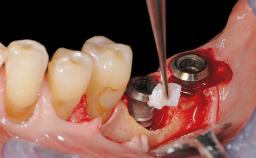

Peri-Implant Mucositis Treatment Outcomes on an Implant with a Submucosal Restoration Margin

Mauricio Araujo and Flauvia Matarazzo present this straightforward clinical case, demonstrating the potential effect of implant placement depth on the resolution of peri-implant treatment. A 42-year-old systemically healthy female patient, a non-smoker with no history of periodontitis, was treated at the Dental Clinic at the State University of Maringá, Brazil between 2008 and 2009, when she received five implants restored with single crowns at sites 14, 26, 27, 36, and 46. After delivery of the implant-supported prosthetic restorations, the patient was enrolled in the supportive peri-implant therapy (SPiT) maintenance program at the same university.